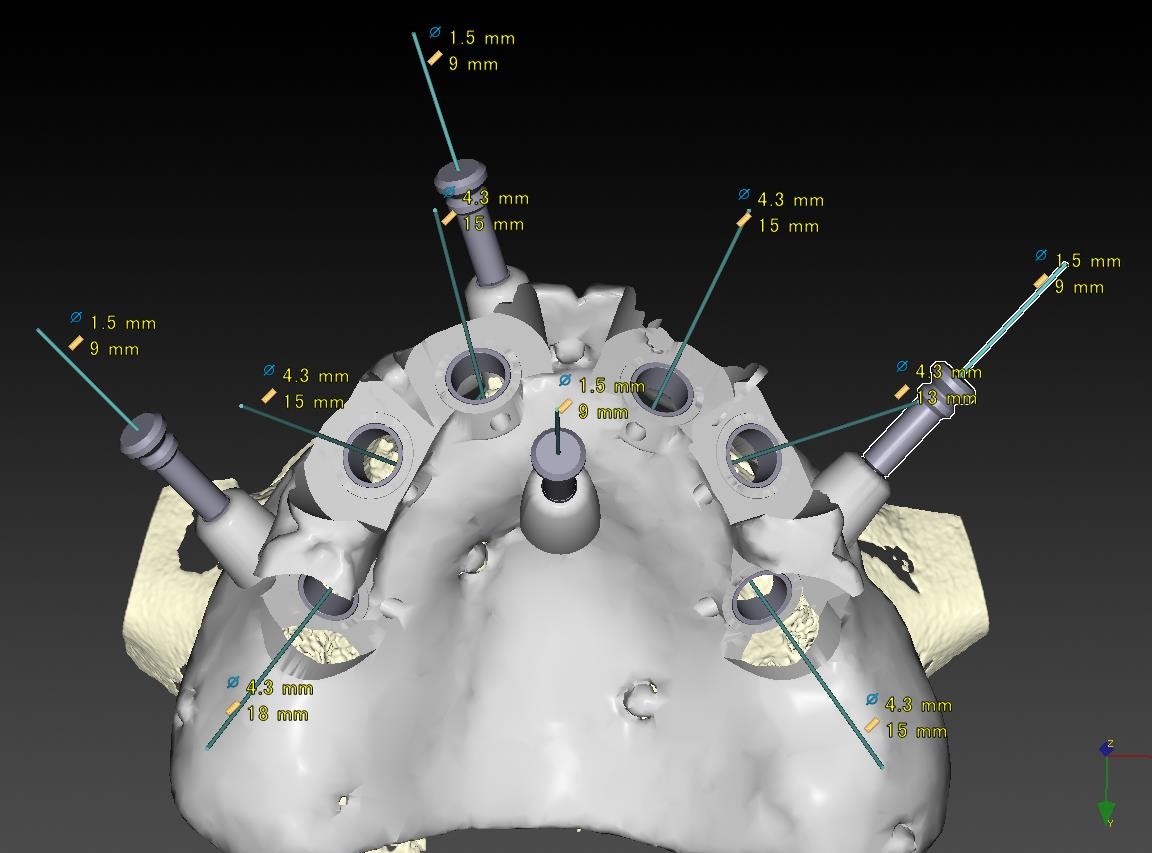

症例11

50代 男性 なんでも食べられるようになりたい

術前咬合面

術前咬合面

術後咬合面

術後咬合面

術前シミュレーション1

術前シミュレーション1

術前シミュレーション2

術前シミュレーション2

サージカルテンプレート

サージカルテンプレート

| 主訴 | 自分が一番元気に、何でも食べられる父親でいたい。家族との食事の時間が人生ですごく大切で、何とかしたい、と思っていた。 |

|---|---|

| 年代・性別 | 50代 男性 |

| 治療部位 | 上顎6~6 |

| 治療費用 |

インプラント手術料 |

| 手術回数 | 1回 |

| 治療期間 | 4ヶ月 |

| 手術時間 | 180分 |

| 治療回数 | 10回 |